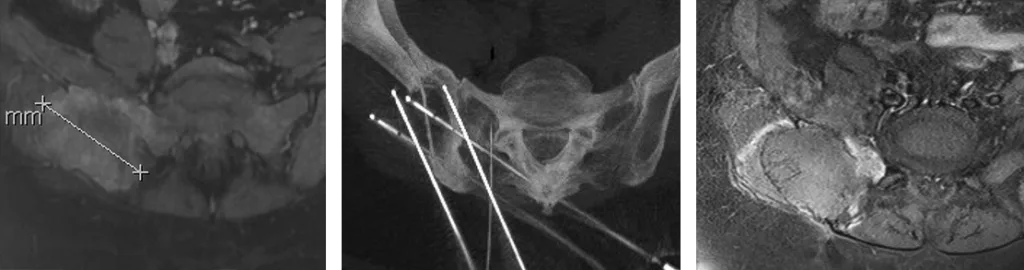

Figure 2 : Métastase osseuse iliaque droite d’un hépatocarcinome, traitée par cryothérapie percutanée

Imageries en coupe axiale pré (IRM), per (scanner) et post (IRM) traitement